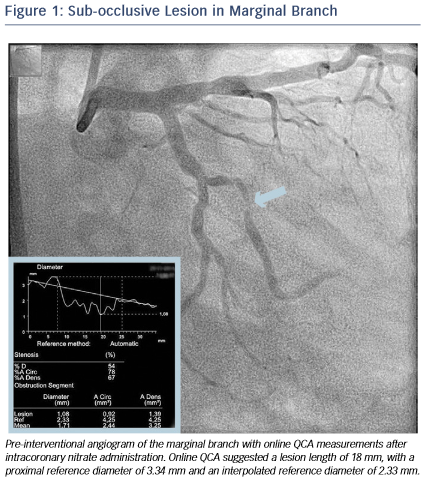

A 46-year-old male without cardiovascular history underwent coronary catheterisation for non-ST elevated myocardial infarction. Angiogram showed a sub-occlusive lesion in the marginal branch that was considered the culprit (see Figure 1), with an online measured interpolated reference diameter of 2.33 mm by Quantitative Coronary Angiography (QCA), while the lesion length was 18 mm.